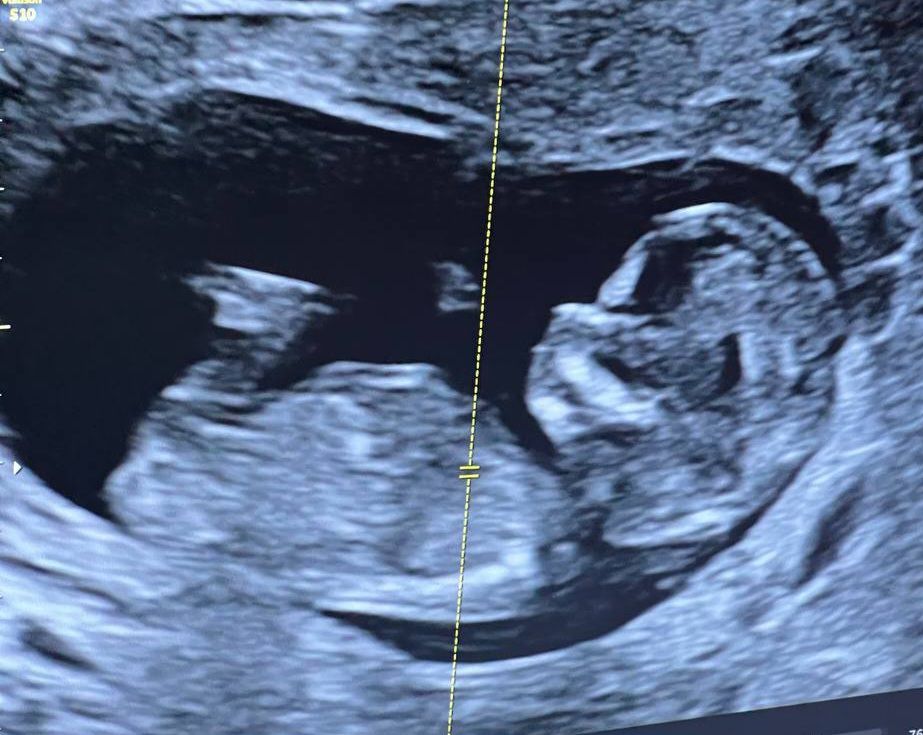

12 недель скрининг гадаем пол

Девочка, половой бугорок параллельно спинке 🌸

Девчушка скорее всего у вас😌

Бугорка не видно, но думаю, что девочка)) Напишите потом ответ, интересно 😊